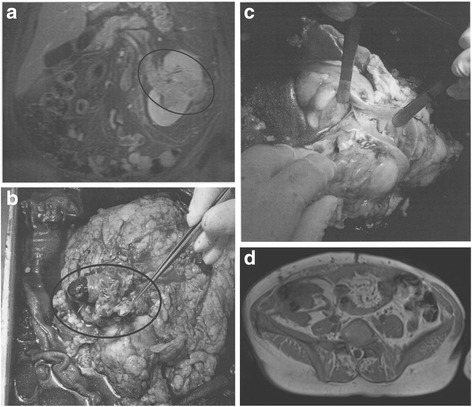

The tumor-bearing kidney was then perfused back-table with cold storage solution, and the resection of the tumor and reconstruction was performed in iced water (picture series Fig. 1). After a conventional Gibson incision, the kidney was transplanted into the ipsi- or contralateral iliac fossa by means of end-to-side vascular anastomoses to the external or common iliac vessels, with non-absorbable 6–0 sutures. The ureter was implanted into the bladder and stented with a double-J ureteral stent in an extravescial uretereroneocystostomy (modified Lich-Gregory technique). In the UTUC cases, a pyelovesicostomy was performed and stented with a mono-J stent which was placed via the bladder as a percutaneous pyelovesicocutaneostomy.

Fig. 1.

a Initial MRI scan PADUA 12p. b Tumor thrombus occupying the renal vein. c Back-table tumor resection and renal reconstruction. d MRI scan showing tumor-recurrence laterally in the autotransplanted kidney in the right iliac fossa. a–d MRI-images and photographs demonstrating a rare case of an extensive clear cell renal cell carcinoma of the lower pole, extending into the renal hilum and forming a venous tumor thrombus in the inferior vena cava grades PADUA 12p (a). A radical nephrectomy, cavotomy, and tumor-thrombectomy were performed (b). In ice water, a tumor resection and renal reconstruction was undertaken (c) followed by autotransplantation. Local recurrence occurred at 48 months, and a partial nephrectomy of the autotransplanted kidney was undertaken. Finally at 105 months, a nephrectomy was performed for a second recurrence (d). At 42 months after nephrectomy, a systemic therapy was introduced for metastases

The exceptional case of one patient suffering from a 8 × 6 × 6 cm large, centrally located tumor in a left solitary kidney was already published in 2007 [12]. A detailed photo-series of this case is presented in Fig. 1.

After 48 months, this patient underwent a partial nephrectomy of the auto-transplanted kidney due to local recurrence of the tumor (Fig. 1d). After a second recurrence, a radical nephrectomy was performed 105 months post-KAT. Histology of the resected kidney described the tumor as pT3a, pNX, L0, V0, Pn0, R0 clear cell RCC. The patient is alive 42 months later, on permanent hemodialysis and on targeted therapy (pazopanib) for an unresectable local tumor relapse. To our knowledge, this patient is the only one of the 12 patients included in our series who required permanent hemodialysis after KAT.